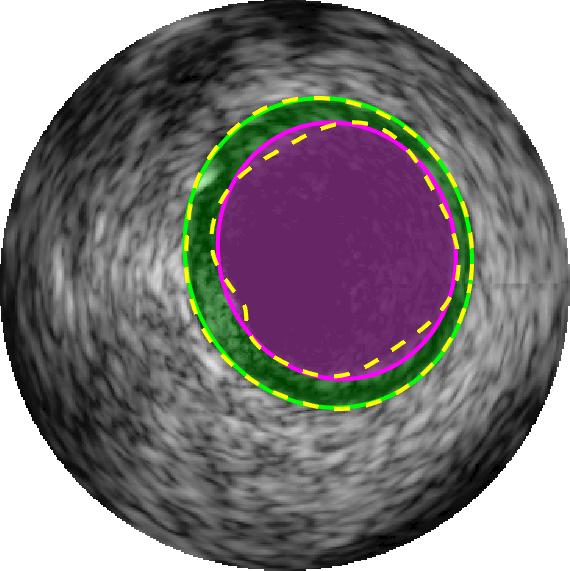

Qualitative evaluations are illustrated in Figure 4 and show the successful segmentation results of the proposed EREL selection strategy for 20 IVUS frames. The lumen areas are highlighted by the magenta colour while the media regions are green. Also, the manually annotated contours for both lumen and media are drawn as yellow dashed lines. As we can see, the chosen frames contain a variety of lumen and media morphologies.